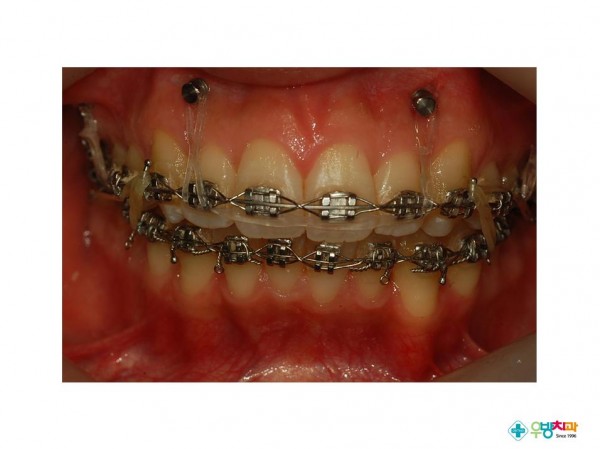

[Gummy smile, protrusion 환자 적용]

Nonextraction treatment with temporary skeletal anchorage devices to correct a Class II Division 2 malocclusion with excessive2.pdf